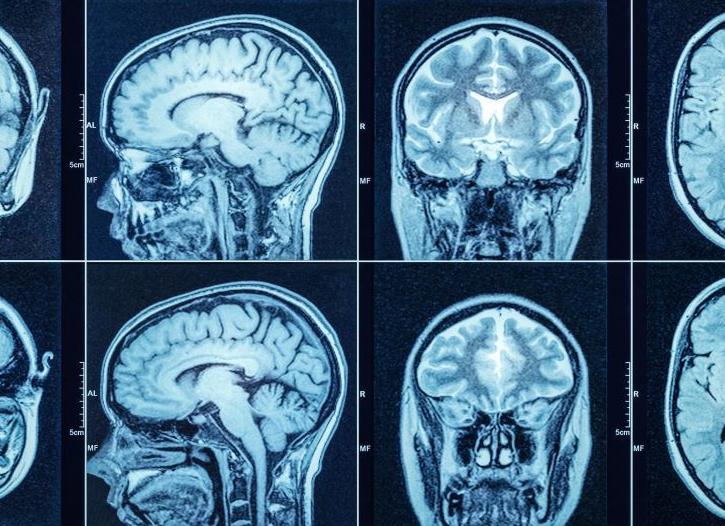

Так выглядит снимок КТ.

Сейчас большую популярность среди диагностических методов исследования мозговых структур имеет компьютерная томография головного мозга. Рентгеновское изучение дает возможность получения серии послойных срезов в разных плоскостях. Изображение получается с помощью специального рентгеновского оборудования и обрабатывается компьютером.

Обследование проводится в сагиттальной, фронтальной и аксиальной плоскостях. Изображение исследуемого органа предоставляется на черно-белых снимках, оно может быть в виде модели черепной коробки и головного мозга.

По этим результатам специалист оценивает расположение тканевых и костных структур, сосудов и многих других элементов. И может оценивать взаимодействие патологических участков и здоровых.

Все ткани и области мозга имеют разную степень плотности, что отображается на поглощаемости рентгеновских лучей. Например, светлая часть на снимке, может свидетельствовать о внутричерепном кровотечении, а затемненная – о наличии новообразований.

Помимо цвета оценивается размер структур, изменение тканей, увеличение или уменьшение просвета сосудов. Для получения более детальных снимков используют контрастное вещество. Оно необходимо для выявления опухолевых образований, тромбов, нарушений кровоснабжения.